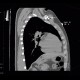

Both CT sections and radiographs show a foreign body of metallic density with metallic artifacts on CT which is lodged in the chest wall anteriorly to the sternal end of the left collar bone.